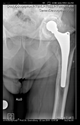

The guiding wire was inserted and controlled with fluoroscopy flashes (Figure 4). The drilling and reaming were carried out in accordance with the recommendations:

Figure 4.

The biocompatible aiming device after insertion of the guiding wire.

The radiological examination allowed us to verify the close bone-to-implant contact and the unchanged position of the implant during follow-up.

In all the cases operated with the above-described targeting procedure, the stems of the cups remained between the cortical bone surfaces without perforation of the linea terminalis, as shown by postoperative radiographs. There were no complicated surgical situations. In 16 cases, the wound healings were uneventful, and the hips were able to bear weight again after postoperative rehabilitation.